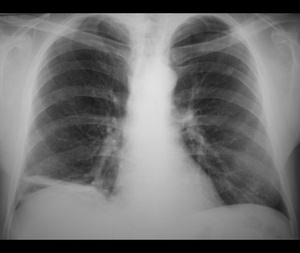

- Рентгенологическое исследование легких. Позволяет выявить заболевание на начальных этапах и провести дифференциальную диагностику, например, с раком легкого, имеющим сходную симптоматику. Главным признаком пневмофиброза является усиление и деформация легочного рисунка, расширение сосудистого пучка и тени с неровными заостренными контурами. Запущенный пневмофиброз выглядит на снимке в виде «пчелиных сот», то есть видны полые и уплотненные участки, чередующиеся друг с другом или/и рубцовых деформаций корней легких (пневмофиброз прикорневой),